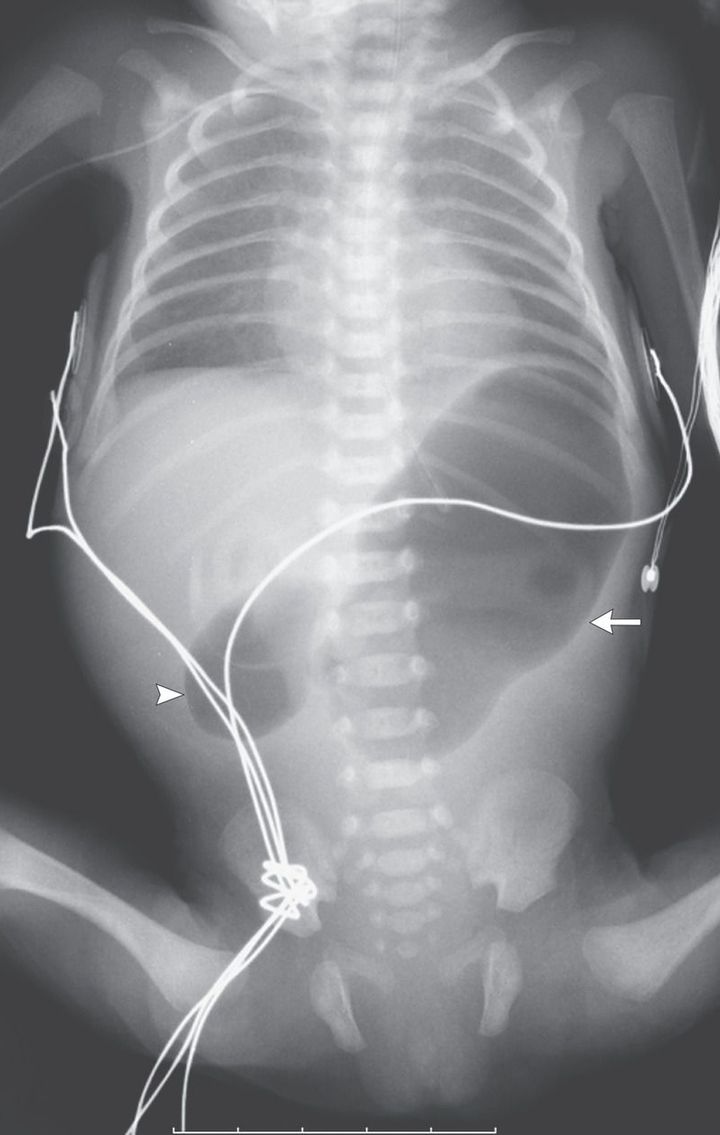

A girl weighing 1080 g was born at a gestational age of 29 weeks because of spontaneous premature rupture of membranes. Enteral feeding through a nasogastric tube was started 8 hours after birth but was not tolerated. The infant's condition deteriorated, with ongoing episodes of nonbilious vomiting and a lack of stools since birth. The physical examination showed mild upper abdominal distention, with apparent discomfort on abdominal palpation. Abdominal radiography showed the double-bubble sign — a distended stomach (arrow) and proximal duodenum (arrowhead) — which is pathognomonic of congenital duodenal obstruction. There was no air distal to the level of obstruction in the D2 segment of the duodenum. Laparoscopy showed duodenal atresia type 1, which was repaired with a diamond-shaped duodenal anastomosis. Oral feedings were initiated successfully on the seventh postoperative day. The postoperative period was uneventful.